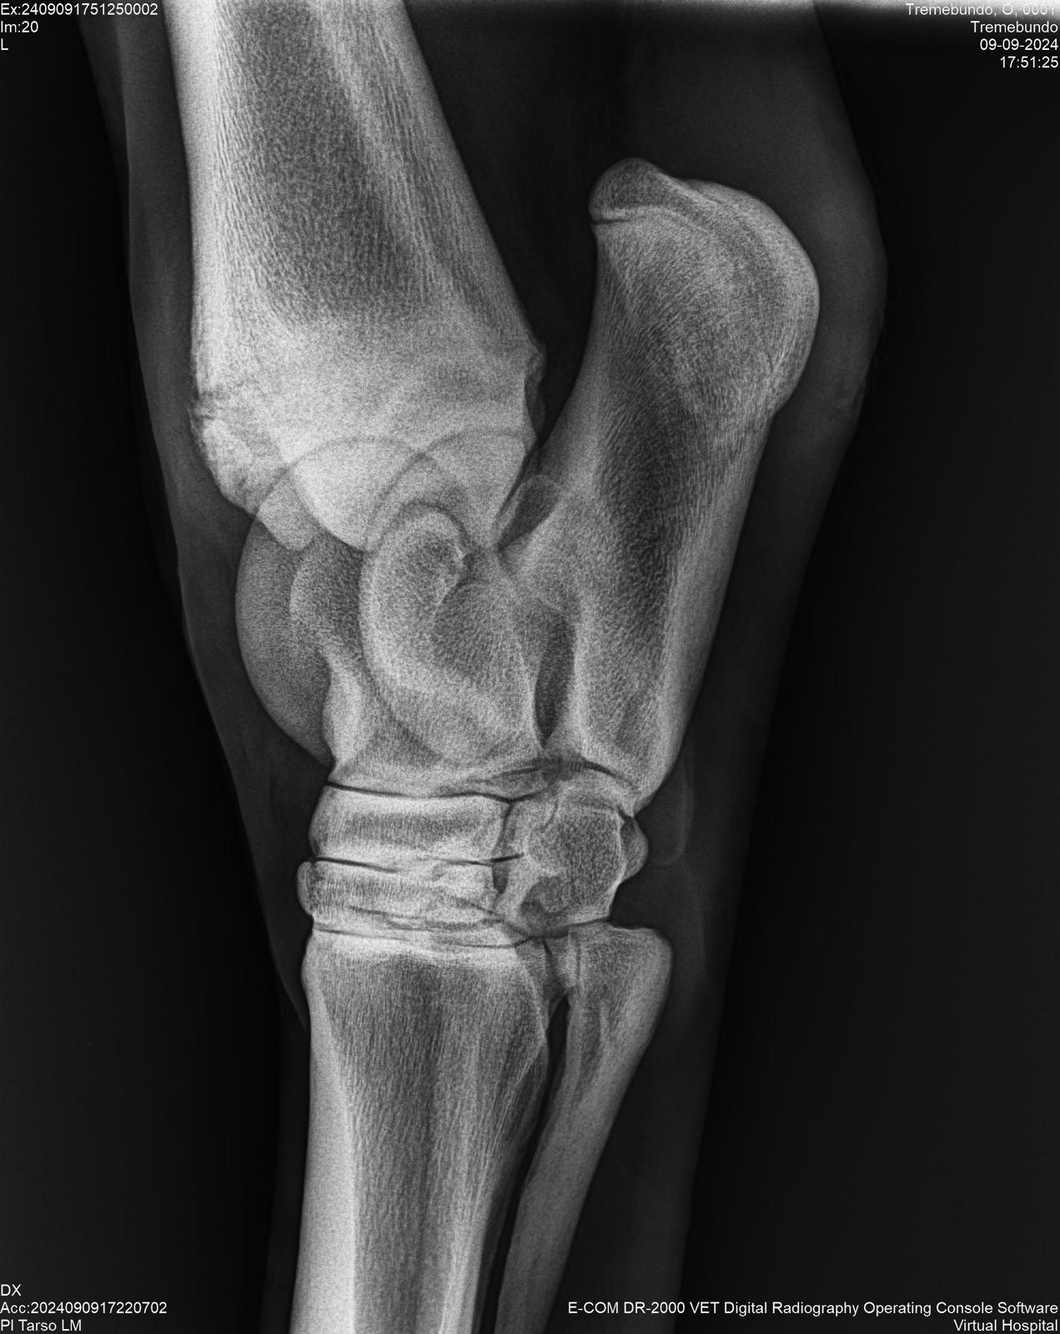

LOTE 37, TREMEBUNDO

Generacion 2022